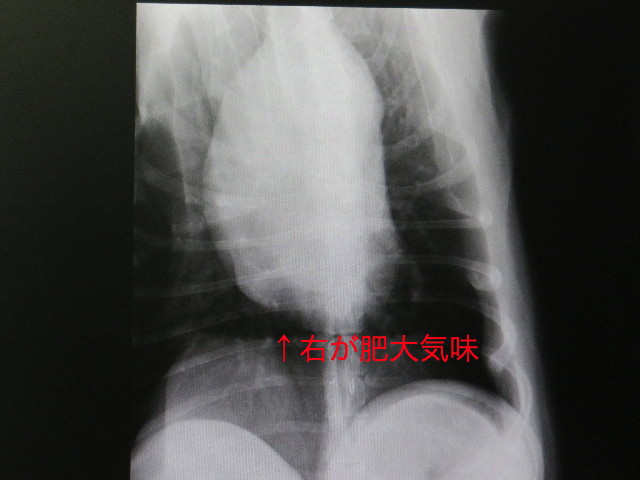

●右眼に眼底出血もありましたし、(腫瘍ができやすい)ゴールデンだし....ということで、久しぶりに【胸のレントゲン】を撮りましうということに。

結果は、特に大きな問題はありませんでしたが

もいちゃんの心臓の位置(というか形)は以前から“寝ていて”、右心室(だったかな?)が肥大気味とのこと。

.....たぶん、今回はじめてききました(ToT)ゞ

以前撮ったレントゲンとほとんど変わっていませんが、言われてみれば確かに右が大きいです。

でも、胸部レントゲンでは、けっこう悪い所や腫瘍等はないので良かったです。(ホッ♪)